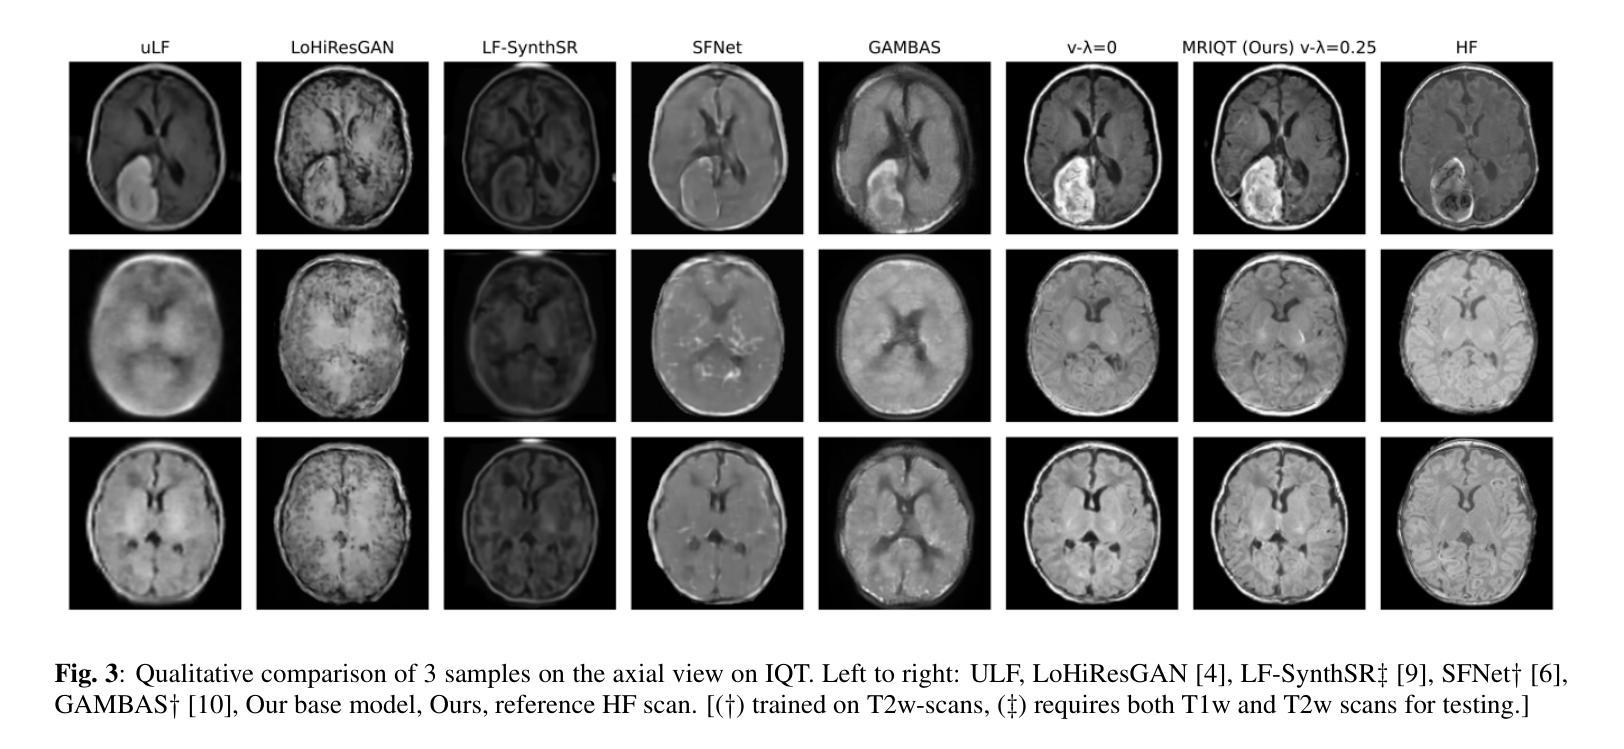

MRIQT: Physics-Aware Diffusion Model for Image Quality Transfer in Neonatal Ultra-Low-Field MRI

Authors:Malek Al Abed, Sebiha Demir, Anne Groteklaes, Elodie Germani, Shahrooz Faghihroohi, Hemmen Sabir, Shadi Albarqouni

Portable ultra-low-field MRI (uLF-MRI, 0.064 T) offers accessible neuroimaging for neonatal care but suffers from low signal-to-noise ratio and poor diagnostic quality compared to high-field (HF) MRI. We propose MRIQT, a 3D conditional diffusion framework for image quality transfer (IQT) from uLF to HF MRI. MRIQT combines realistic K-space degradation for physics-consistent uLF simulation, v-prediction with classifier-free guidance for stable image-to-image generation, and an SNR-weighted 3D perceptual loss for anatomical fidelity. The model denoises from a noised uLF input conditioned on the same scan, leveraging volumetric attention-UNet architecture for structure-preserving translation. Trained on a neonatal cohort with diverse pathologies, MRIQT surpasses recent GAN and CNN baselines in PSNR 15.3% with 1.78% over the state of the art, while physicians rated 85% of its outputs as good quality with clear pathology present. MRIQT enables high-fidelity, diffusion-based enhancement of portable ultra-low-field (uLF) MRI for deliable neonatal brain assessment.

便携式超低场磁共振成像(uLF-MRI,0.064T)为新生儿护理提供了可访问的神经成像,但与高场(HF)MRI相比,其信噪比低,诊断质量较差。我们提出了MRIQT,这是一个用于从uLF到HF MRI的图像质量转移(IQT)的3D条件扩散框架。MRIQT结合了逼真的K空间退化进行物理一致的uLF模拟、v预测与无分类器指导的稳定图像到图像生成,以及信噪比加权的3D感知损失以实现解剖保真度。该模型从受噪声影响的uLF输入中去除噪声,该输入以相同的扫描为条件,利用体积注意力U-Net架构进行结构保留翻译。MRIQT在新生儿队列(具有多种病理)上进行了训练,在PSNR上超越了最近的GAN和CNN基准测试,提高了15.3%,并且较目前最佳水平提高了1.78%,而医生认为其输出的85%具有良好的质量,病理清晰可见。MRIQT实现了基于扩散的高保真增强便携式超低场(uLF)MRI,可用于可靠的新生儿脑评估。

便携式超低场磁共振成像(uLF-MRI,0.064T)在新生儿护理中提供可访问的神经成像,但与高场(HF)MRI相比,其信噪比低,诊断质量较差。本文提出MRIQT,一种从uLF到HF MRI的图像质量转移(IQT)的3D条件扩散框架。MRIQT结合真实的K空间退化进行物理一致的uLF模拟、v预测与无分类器引导的稳定图像到图像生成,以及信噪比加权的3D感知损失,以保证解剖真实性。该模型从带噪声的uLF输入中去除噪声,并以相同的扫描为条件,利用体积注意力U-Net架构进行结构保留翻译。在具有多种病理的新生儿队列上进行训练,MRIQT在峰值信噪比(PSNR)上超越了最近的生成对抗网络(GAN)和卷积神经网络(CNN)基准测试,达到了15.3%的提升,并较目前最佳水平高出1.78%。医师评价其输出的图像中,85%具有良好的质量和清晰的病理表现。MRIQT实现了基于扩散的便携式超低场(uLF)MRI高保真增强,可用于可靠的新生儿脑评估。